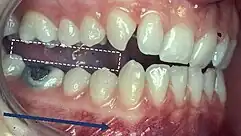

Classification of occlusion and malocclusion plays an important role in diagnosis and treatment planning in orthodontics. In order to describe the relationship of the maxillary molars to the mandibular molars, the Angle’s classification of malocclusion has commonly been used for many years.[8] This system has also been adapted in an attempt to classify the relationship between the incisors of the two arches.[9]

When describing the relationship between maxillary and mandibular incisors, the following categories make up Angle's incisal relationship classification:

- Class I: Mandibular incisors contact the maxillary incisors in the middle third or on the cingulum of the palatal surface

- Class II: Mandibular incisors contact the maxillary incisors on the palatal surface, in the gingival third or posterior to the cingulum. This class may be further subdivided into division I and division II:

- Class III: Mandibular incisors occlude with the maxillary incisors on the palatal surface, in the incisal third specifically or anterior to the cingulum

- In some cases the overjet is reversed (<0mm) and the mandibular incisors lie anterior to the maxillary incisors

Molar Relationship

When discussing the occlusion of the posterior teeth, the classification refers to the first molars and may be divided into three categories:

- Class I: The mandibular first molar occludes mesially to the maxillary first molar, with the mesiobuccal cusp of maxillary first molar occluding in the buccal groove of mandibular first molar

- Class II: The mesiobuccal cusp of the maxillary first molar occludes anterior to the buccal groove of the mandibular first molar

- Class III: If the mesiobuccal cusp of the maxillary first molar occludes posterior to the buccal groove of the mandibular first molar[8]

Any deviation from the normal relation of teeth (Class I) is considered a malocclusion.